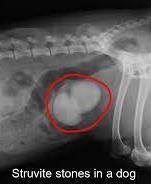

• Struvite stones

• Magnesium ammonium phosphate stones